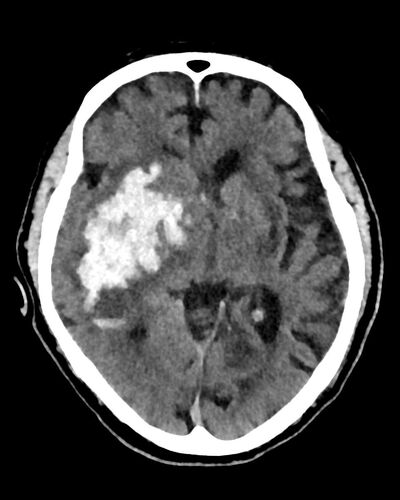

Bei Verdacht auf einen Schlaganfall zum Beispiel zählt jede Minute. Wichtig ist vor allem, schnell zu differenzieren, ob ein verschlossenes Blutgefäß die Symptome verursacht oder eine Hirnblutung. „Die Symptome sind in beiden Fällen ähnlich, die Konsequenzen aber ganz andere“, betont Glüer. Im ersten Fall muss die Durchblutung des betroffenen Gehirnbereichs durch Gabe spezieller Medikamente schnellstmöglich wiederhergestellt werden. Im zweiten Fall muss die Blutung gestoppt und Schädigungen durch das austretende Blut müssen vermieden werden.

CT-Aufnahmen des Gehirns von Personen mit Schlaganfall: Hirninfarkt infolge eines Gefäßverschlusses. © Klinik für Radiologie und Neuroradiologie